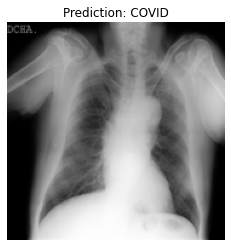

Currently, there is an urgent need for efficient tools to assess the diagnosis of COVID-19 patients. In this project, we propose a constructive solution for detecting and labeling infected tissues on CT lung images of such patients. To cut down false positives our model is trained on 4 types of lung CT images : COVID, Viral Pneumonia, Lung Opacity and normal images to get the best possible results with highest accuracy.

We built it using Tensorflow 2.x using Python. We have developed a Convolutional Neural Network model with an average accuracy of more than 85%. We built the WebApp using Streamlit library for easy interaction with the prediction model.

We are proud that among the top 5 models, one of our models achieved 88.8% accuracy with very low loss.